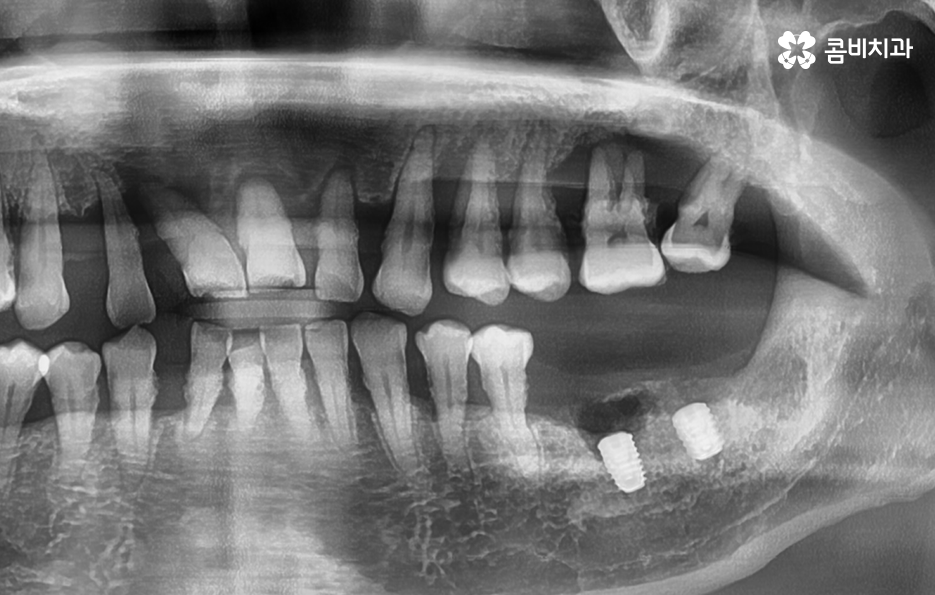

임플란트의 치료 원리를 살펴보면 임플란트는 잇몸 뼈에 심고 골 유착 과정을 통해서 저작력을 얻기 때문에 치료 전과 치료 후 모두 잇몸 상태가 매우 중요한 치료라는 것을 알 수 있어요

잇몸 뼈가 부족한 경우 뼈이식을 통해 임플란트를 식립하기 좋은 잇몸 상태를 만드는 것이 치료 결과에도 중요하며 임플란트의 식립 위치부터 각도, 깊이 등은 치과의 첨단 장비뿐 아니라 치과의사의 경험과 실력이 중요한 부분이기 때문에 임플란트의 전체 과정을 고려하여 비용도 중요하지만 건강한 치료 결과를 위해 종합적으로 따져보고 치과를 선택하시길 권하고 있어요